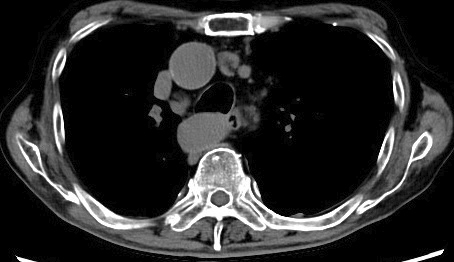

甲氨蝶呤相关的霍奇金淋巴瘤在甲氨蝶呤起始治疗几十年后发生。

Methotrexate-associated Hodgkin Lymphoma Occurring Decades after Methotrexate Initiation.